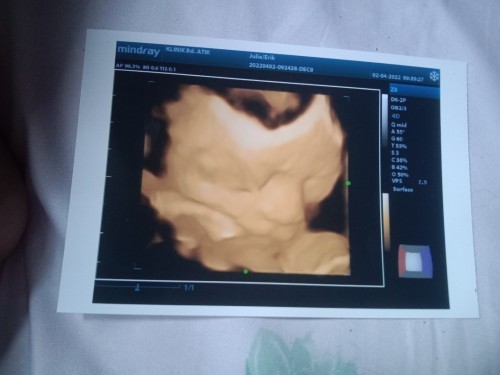

Assalamu'alaikum bund. Gimana puasa ke 2 nya nih. Mau nanya bantu jawab yaa. Kemarin diusg usia janinku 29weeks 6day karena hasil usg bb janinnya sudah 2kg kenapa jadi usianya 31weeks ya bund. Pd usg tm 1 itu pas sesuai hpht. Kebetulan aku nikah tgl 3 dan tgl 5 haidnya. Langsung isi ga haid lagi bulan selanjutnya. Efek tetangga byk gosip yg ga engga. Ortu khawatir aku hamil duluan pdhl ngga gitu bund🥺 sedih bgt rasanya. Gimana jelasinnya ya. Sedangkan kalo hpl emg bisa aja maju atau mundur kan. Harusnya hpl 12 Juni jadi maju pas usg kmrn perkiraan akhir mei atau awal juni. Suruh diet dikurangi yg manis² katanya. Emg kira² yg bikin naik pesat bbj itu apa aja yaa. Perasaan kmrn cuma minum susu hamil atau ngga susu kental manis. Karenaporsi makan masih sedikit. Sehari cuma 2kali juga makannya. Tapi janin malah gemoy gitu bb nya. #bantusharing #ingintahu #pleasehelp #firstbaby